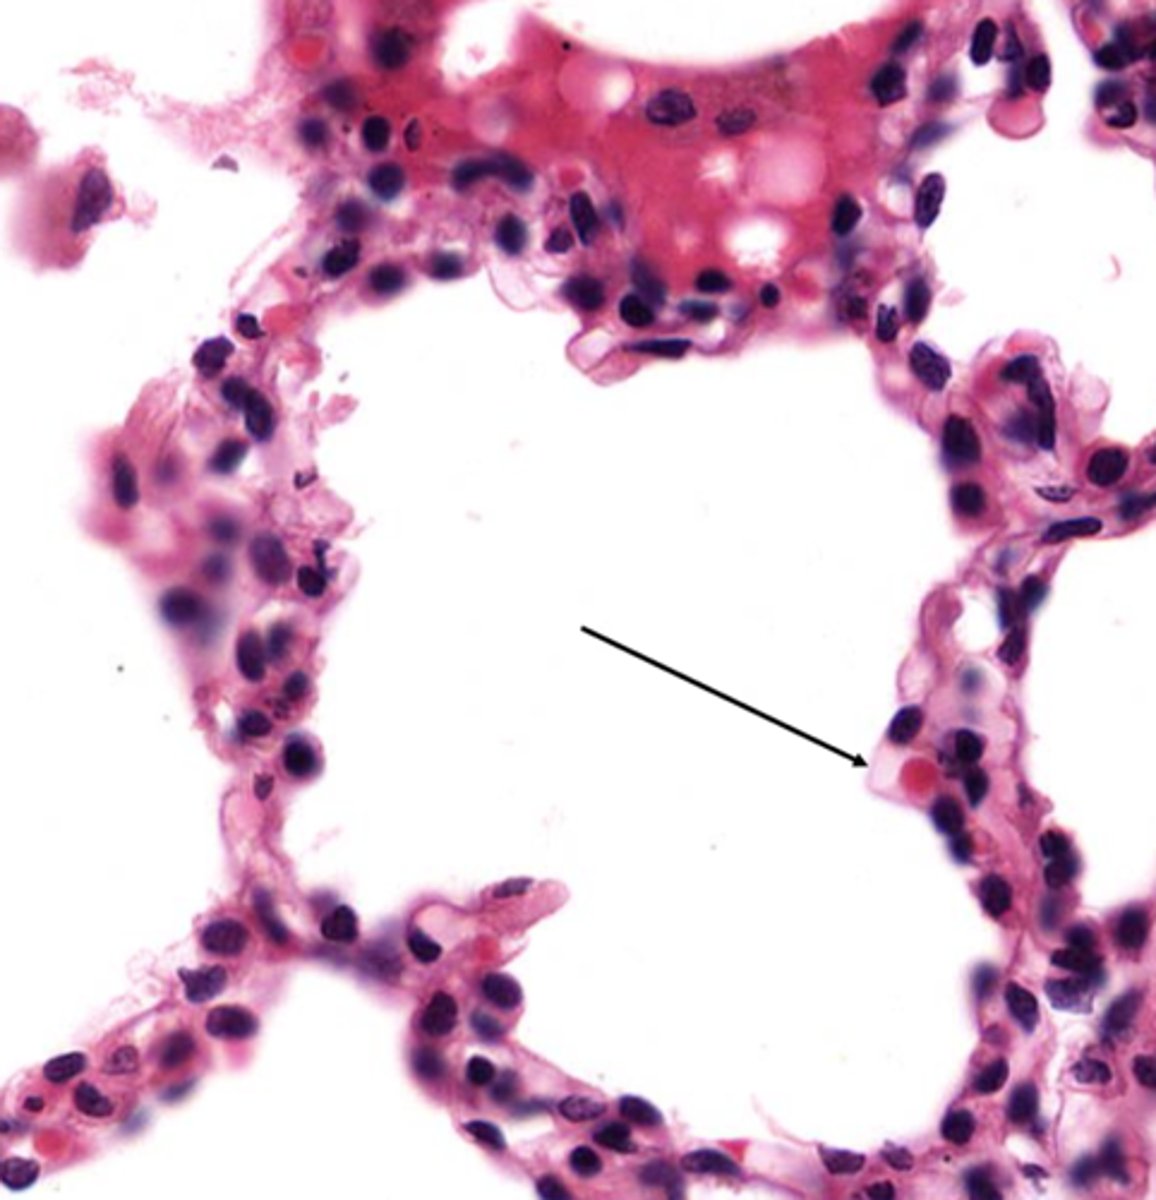

Identify the airway segment between the lines.

alveolar ducts

Identify the starred portion of the airway

alveolar sacs

Identify these unattached cells in this alveolus

pulmonary alveolar macrophages

Name the barrier located here

blood air barrier

What cells make up the blood air barrier

type 1 pneumocyte and endothelial cells